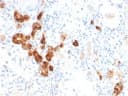

Calbindin Antibody / CALB1

IgG2b κApplications:

ELISA, IHC-PFormat: